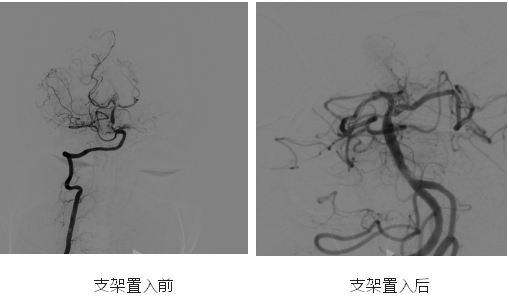

王婆婆此前因反复头晕在当地医院就诊,被确诊为“后循环缺血、基底动脉重度狭窄”。造影显示,其基底动脉下端狭窄达90%,还伴有左侧椎动脉起始部迂曲、左侧椎动脉V3和V4段开窗畸形等复杂血管问题。

经熟人推荐,王婆婆一家找到湖北省第三人民医院神经内科万跃教授团队。团队高度重视,立即反复细致分析评估其血管影像资料,充分论证手术可行性与风险应对方案,最终凭借丰富经验和扎实技术,决定为其行“基底动脉球囊扩张 + 支架置入术”。

“万教授愿意接纳我做手术,我就有了80%的信心,预感手术会成功。”手术前一天,王婆婆拉着管床医生严丹的手激动地说。手术中,王婆婆血管迂曲增加了操作难度,但万跃教授团队默契配合、技术娴熟、心态沉稳,精准完成球囊扩张与支架置入,成功开通基底动脉。